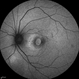

- traumatic macular hole, human amniotic graft

- A 24 year old male patient presented with history of injury at workplace followed by loss of vision. He had a intraocular foreign body with a large traumatic macular hole. Patient was operated and the intraocular foreign body was removed. The hole was too large to close by ILM so an AMG graft was used. Patient regained 20/120 vision.